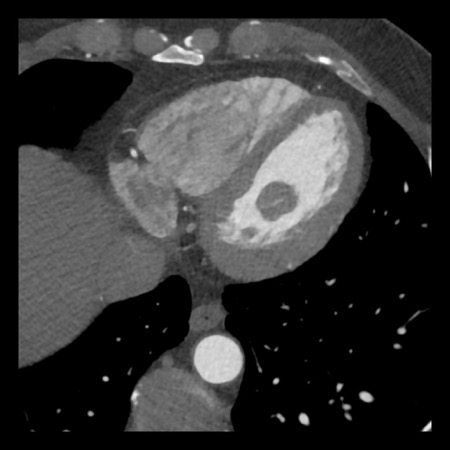

case 4 – CAD-RADS 3/P1/I+ thrombus left ventricle

First, scroll through the CTA images.

How would you describe the findings on the coronary CTA?

The findings are:

- Moderate (50-69%)

stenosis in the proximal LAD caused by a non-calcified plaque. - Variant of

sinoatrial (SA) nodal artery. The artery usually arises from the RCA as a second

branch after the conus artery, however in this case it arises from the LCX,

courses behind the aorta, anastomosing with the right atrium and with a small

branch supplies the SA-node of the heart. - Thrombus in the

apex of the left ventricle. - CTP was performed

in this patient. CTP showed a perfusion defect at stress imaging in the

territory of the LAD (I+), at rest no perfusion defect was visible.

This patient classifies as CAD-RADS 3/P1/I+, which means

this patient requires further investigation.